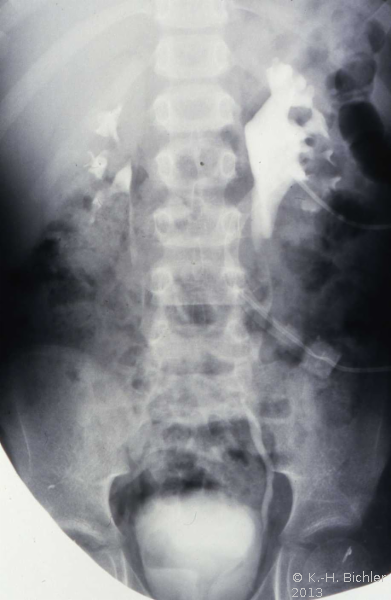

Bei dem 8-jährigen Jungen waren Schmerzen im linken Oberbauch sowie rezidivierende Harnwegsinfekte Ursachen für die Abklärung. sonographisch und röntgenologisch fanden sich Nierenkelchkonkremente in einer Harnstaaungsniere (Abbildungen 21,22,23). Bei der retrograden Sondierung ergab sich ein deutlicher Widerstand in Höhe des Ureterabgangs. Die Freilegung zeigte eine aberrierende Arterie als Abflusshindernis. Nach Durchtrennung des Harnleiters Eröffnung des Nierenbeckens zur Steinentfernung und Abgangsplastik des vorgelagerten Harnleiters. Normalisierung der Abflussverhältnisse.